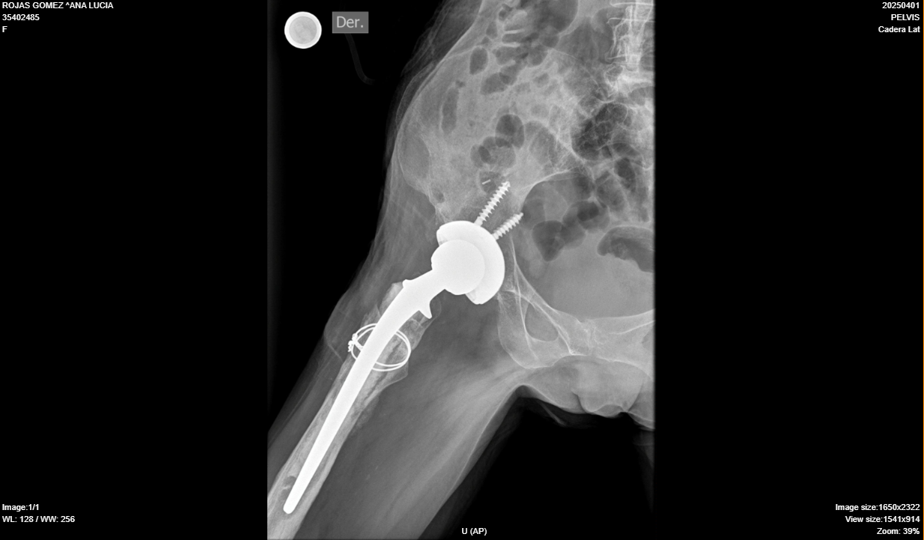

Infección periprotésica de cadera derecha

Rx Der

Protesis de cadera derecha híbrida con signos de aflojamiento del vastago femoral